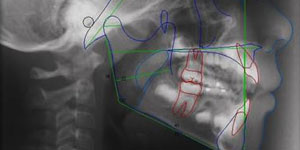

Serviço de Radiologia Dentária

A clínica encontra-se equipada com os mais avançados equipamentos de...

Ortodontia

A ortodontia tem por base a correção da posição dos dentes e maxil...